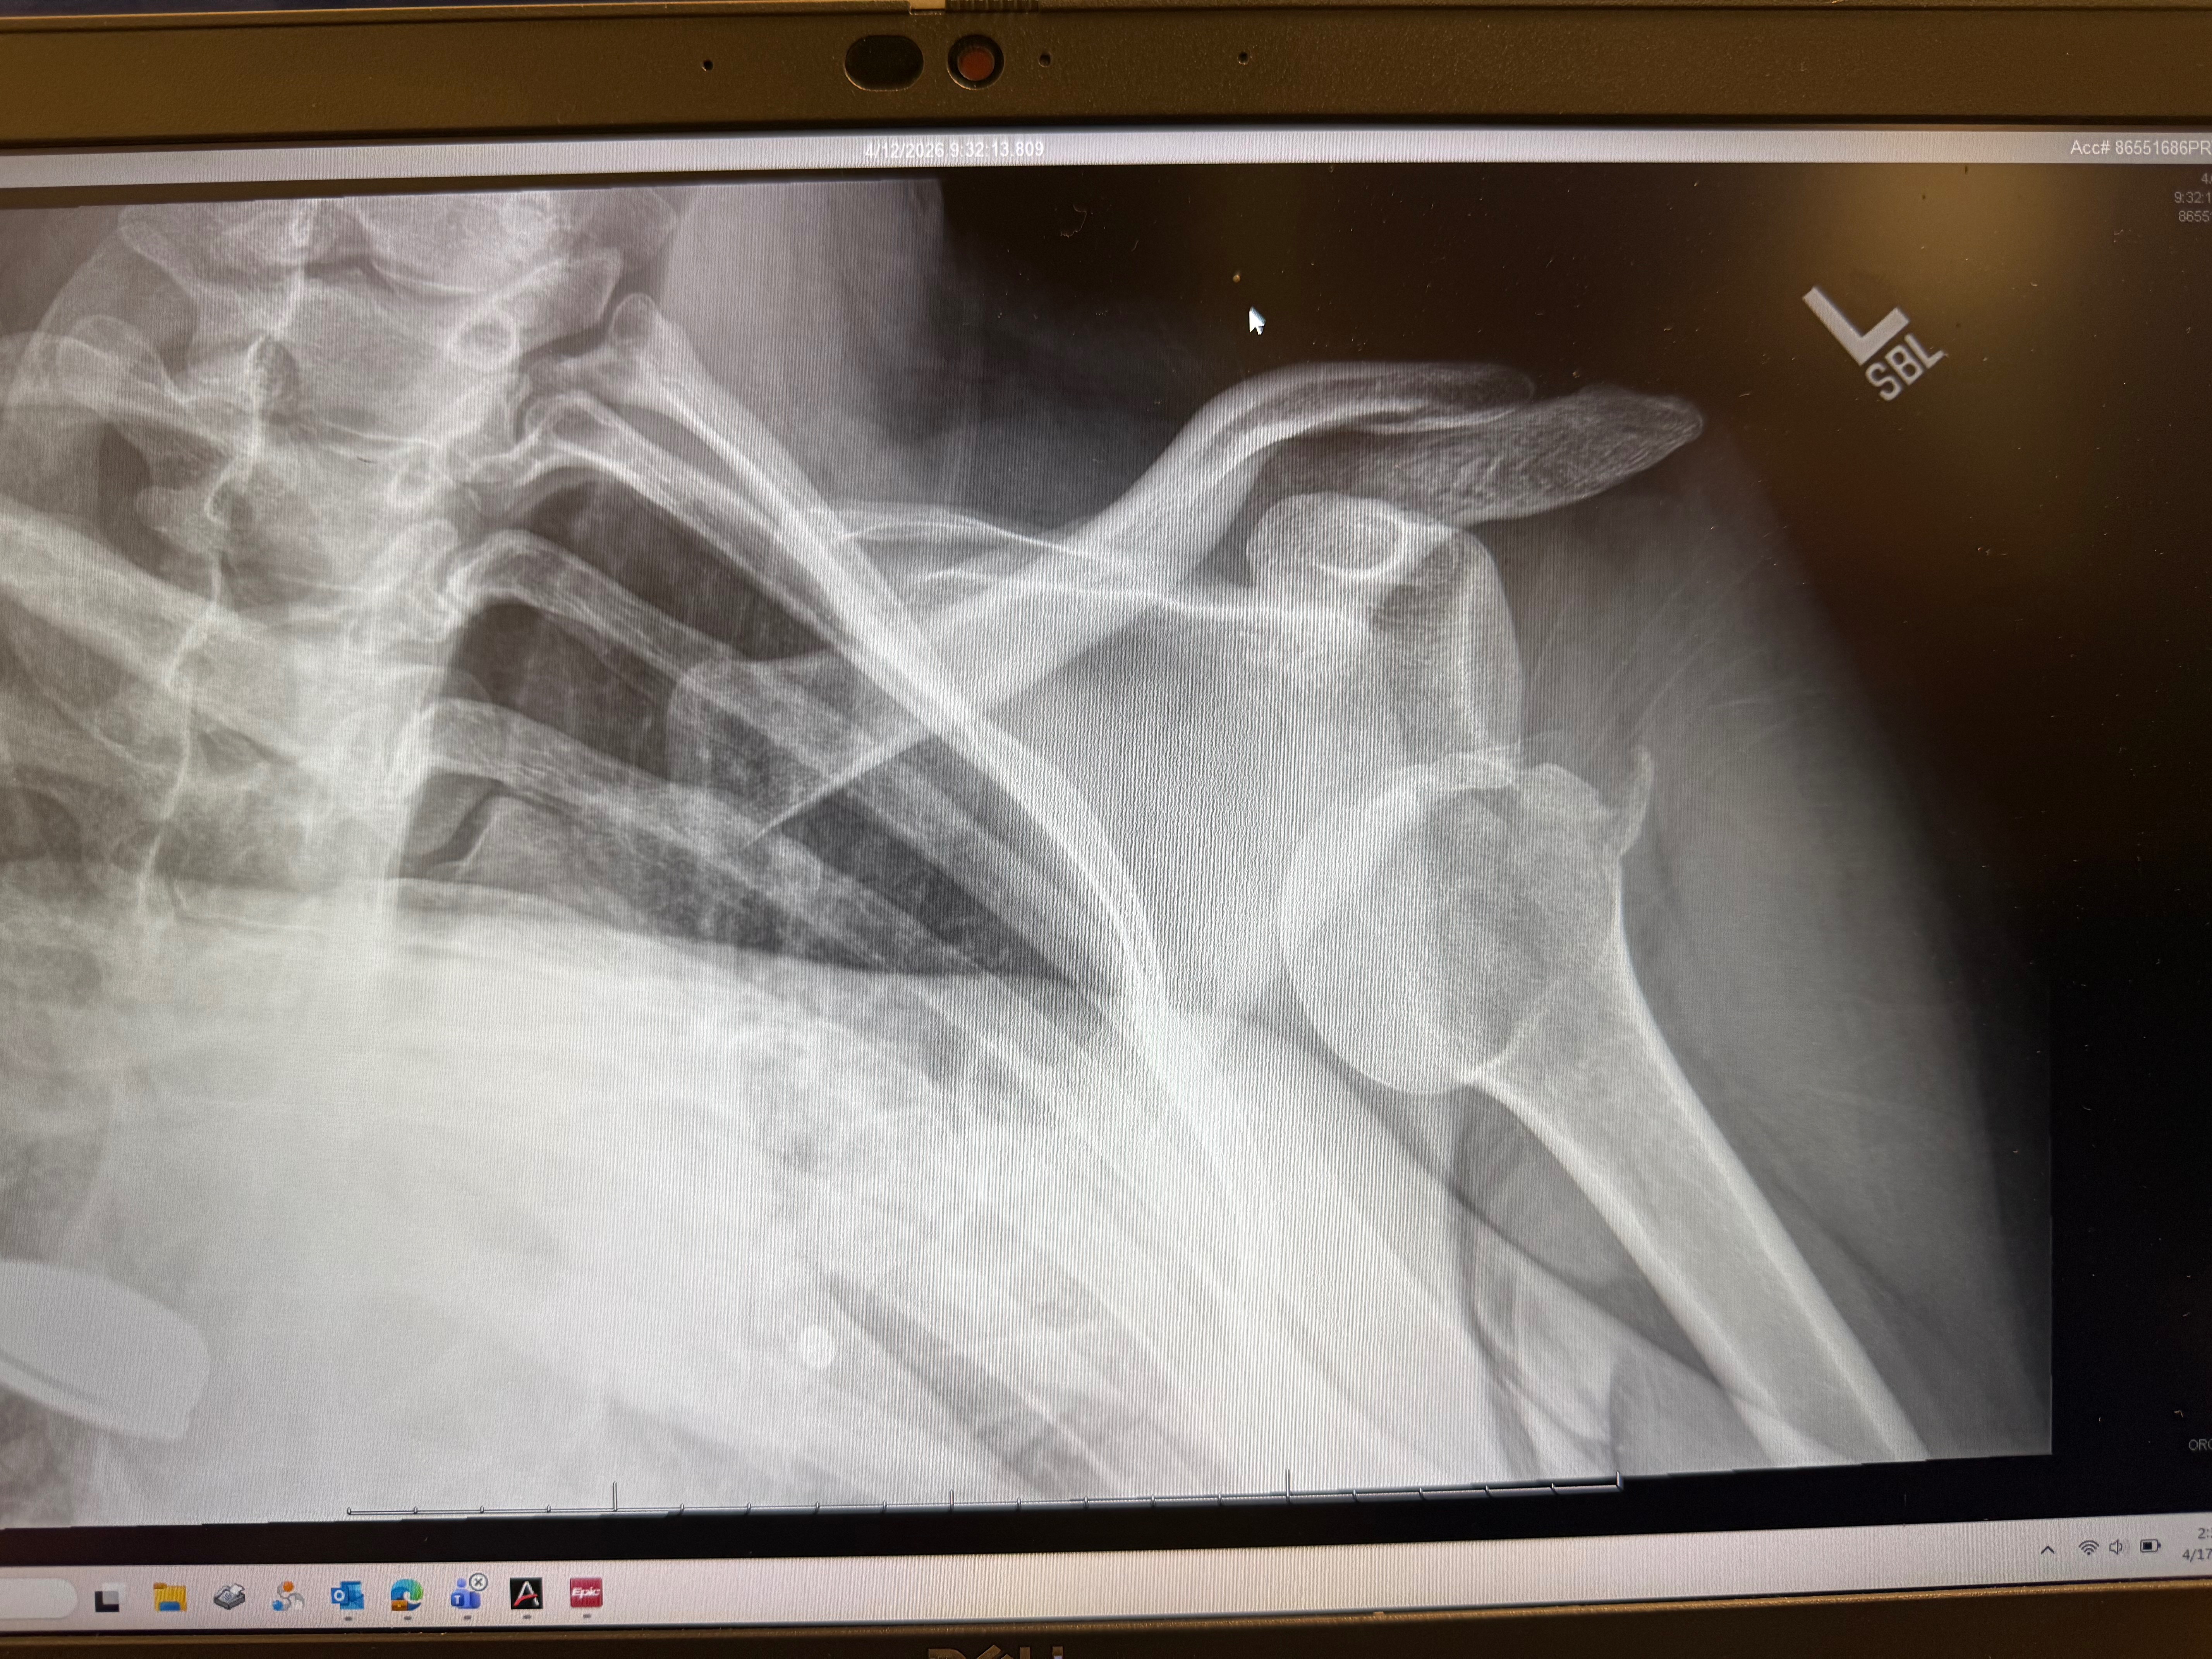

Cait had a scooter accident and broke her humerus on the left side. She is going to be out of work for 6-12 weeks and is a dog groomer. She is also left-handed, so there really won't be a good way for her to work at all, even if we ignored the doctor. We have insurance but can't really afford to have her skip two paychecks. She is very worried about this and we just need some help to cover a couple of paychecks for normal bills.